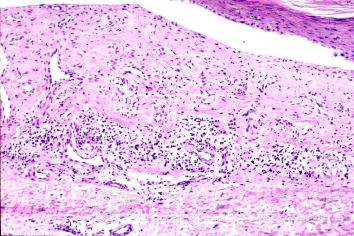

北京京城皮肤医院指出,肌肤敏感是儿童常容易患的过敏性皮肤病。肌肤敏感发病特征为慢性病程。

时轻时重,常反复呈急性或亚急性发作,尤以精神紧张时为甚。常由于急性和亚慢性湿疹处理不当,长期不愈或反复发作转变而来。多局限于某一部位,如手、小腿、肘窝、阴囊、女阴等处,境界明显,炎症不着。